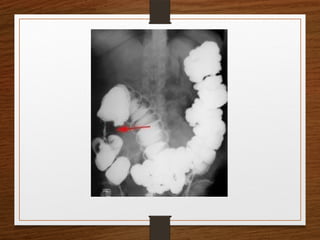

Doubt about the

diagnosis on the plain

radiographs

Contrast enema

• Features seen at the point of torsion include a

smooth, curved tapering of the colonic lumen, like a

hooked beak (the bird of prey sign)

• the mucosal folds often show a ‘screw’ pattern at the

point of twist

Doubt about the diagnosison the plain radiographs Contrast enema

• 33.

Contrast enema • Featuresseen at the point of torsion include a smooth, curved tapering of the colonic lumen, like a hooked beak (the bird of prey sign) • the mucosal folds often show a ‘screw’ pattern at the point of twist